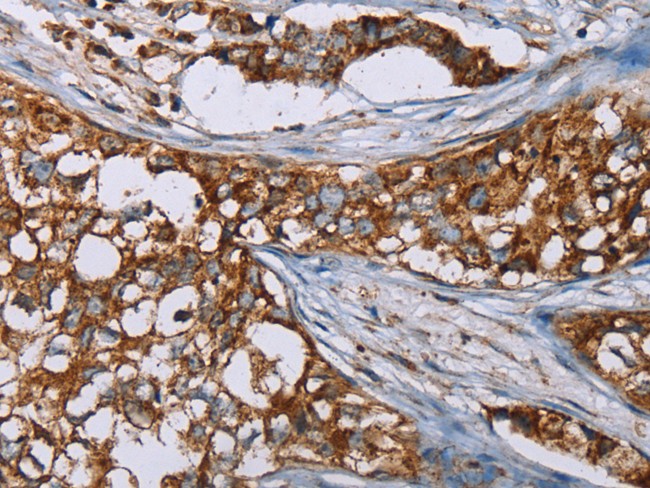

IHC (Immunohiostchemistry)

(Immunohistochemistry of paraffin-embedded Human breast cancer using BMP6 Polyclonal Antibody at dilution of 1:50)